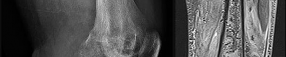

Figures 7a through 7d are the radiograph, MR images, and biopsy specimen of a 35-year-old man who has a painful, slowly enlarging knee mass. Which chromosomal translocation is characteristic of this pathology?

Synovial sarcoma is a soft-tissue sarcoma that usually occurs in young adults. Synovial sarcoma often causes pain, unlike most soft-tissue sarcomas, which generally do not cause pain. Imaging characteristics include soft-tissue calcifications on plain radiographs and a heterogeneous mass that is generally isointense to muscle on T1-weighted images and hyperintense to muscle on T2-weighted images. There are biphasic and monophasic types of synovial sarcoma. The biphasic

type, which is depicted here, has both spindle cell and epithelial components and will stain for both vimentin and cytokeratin. More than 90% of patients with synovial sarcoma have a characteristic genetic translocation of t(X;18), which results in the fusion protein SS18-SSX. This translocation can be stained for use of florescence in situ hybridization technology. t(11;12) is seen in Ewing sarcoma. T(9;22) is seen in extraskeletal myxoid chondrosarcoma. t(12;16) is seen in myxoid liposarcoma.